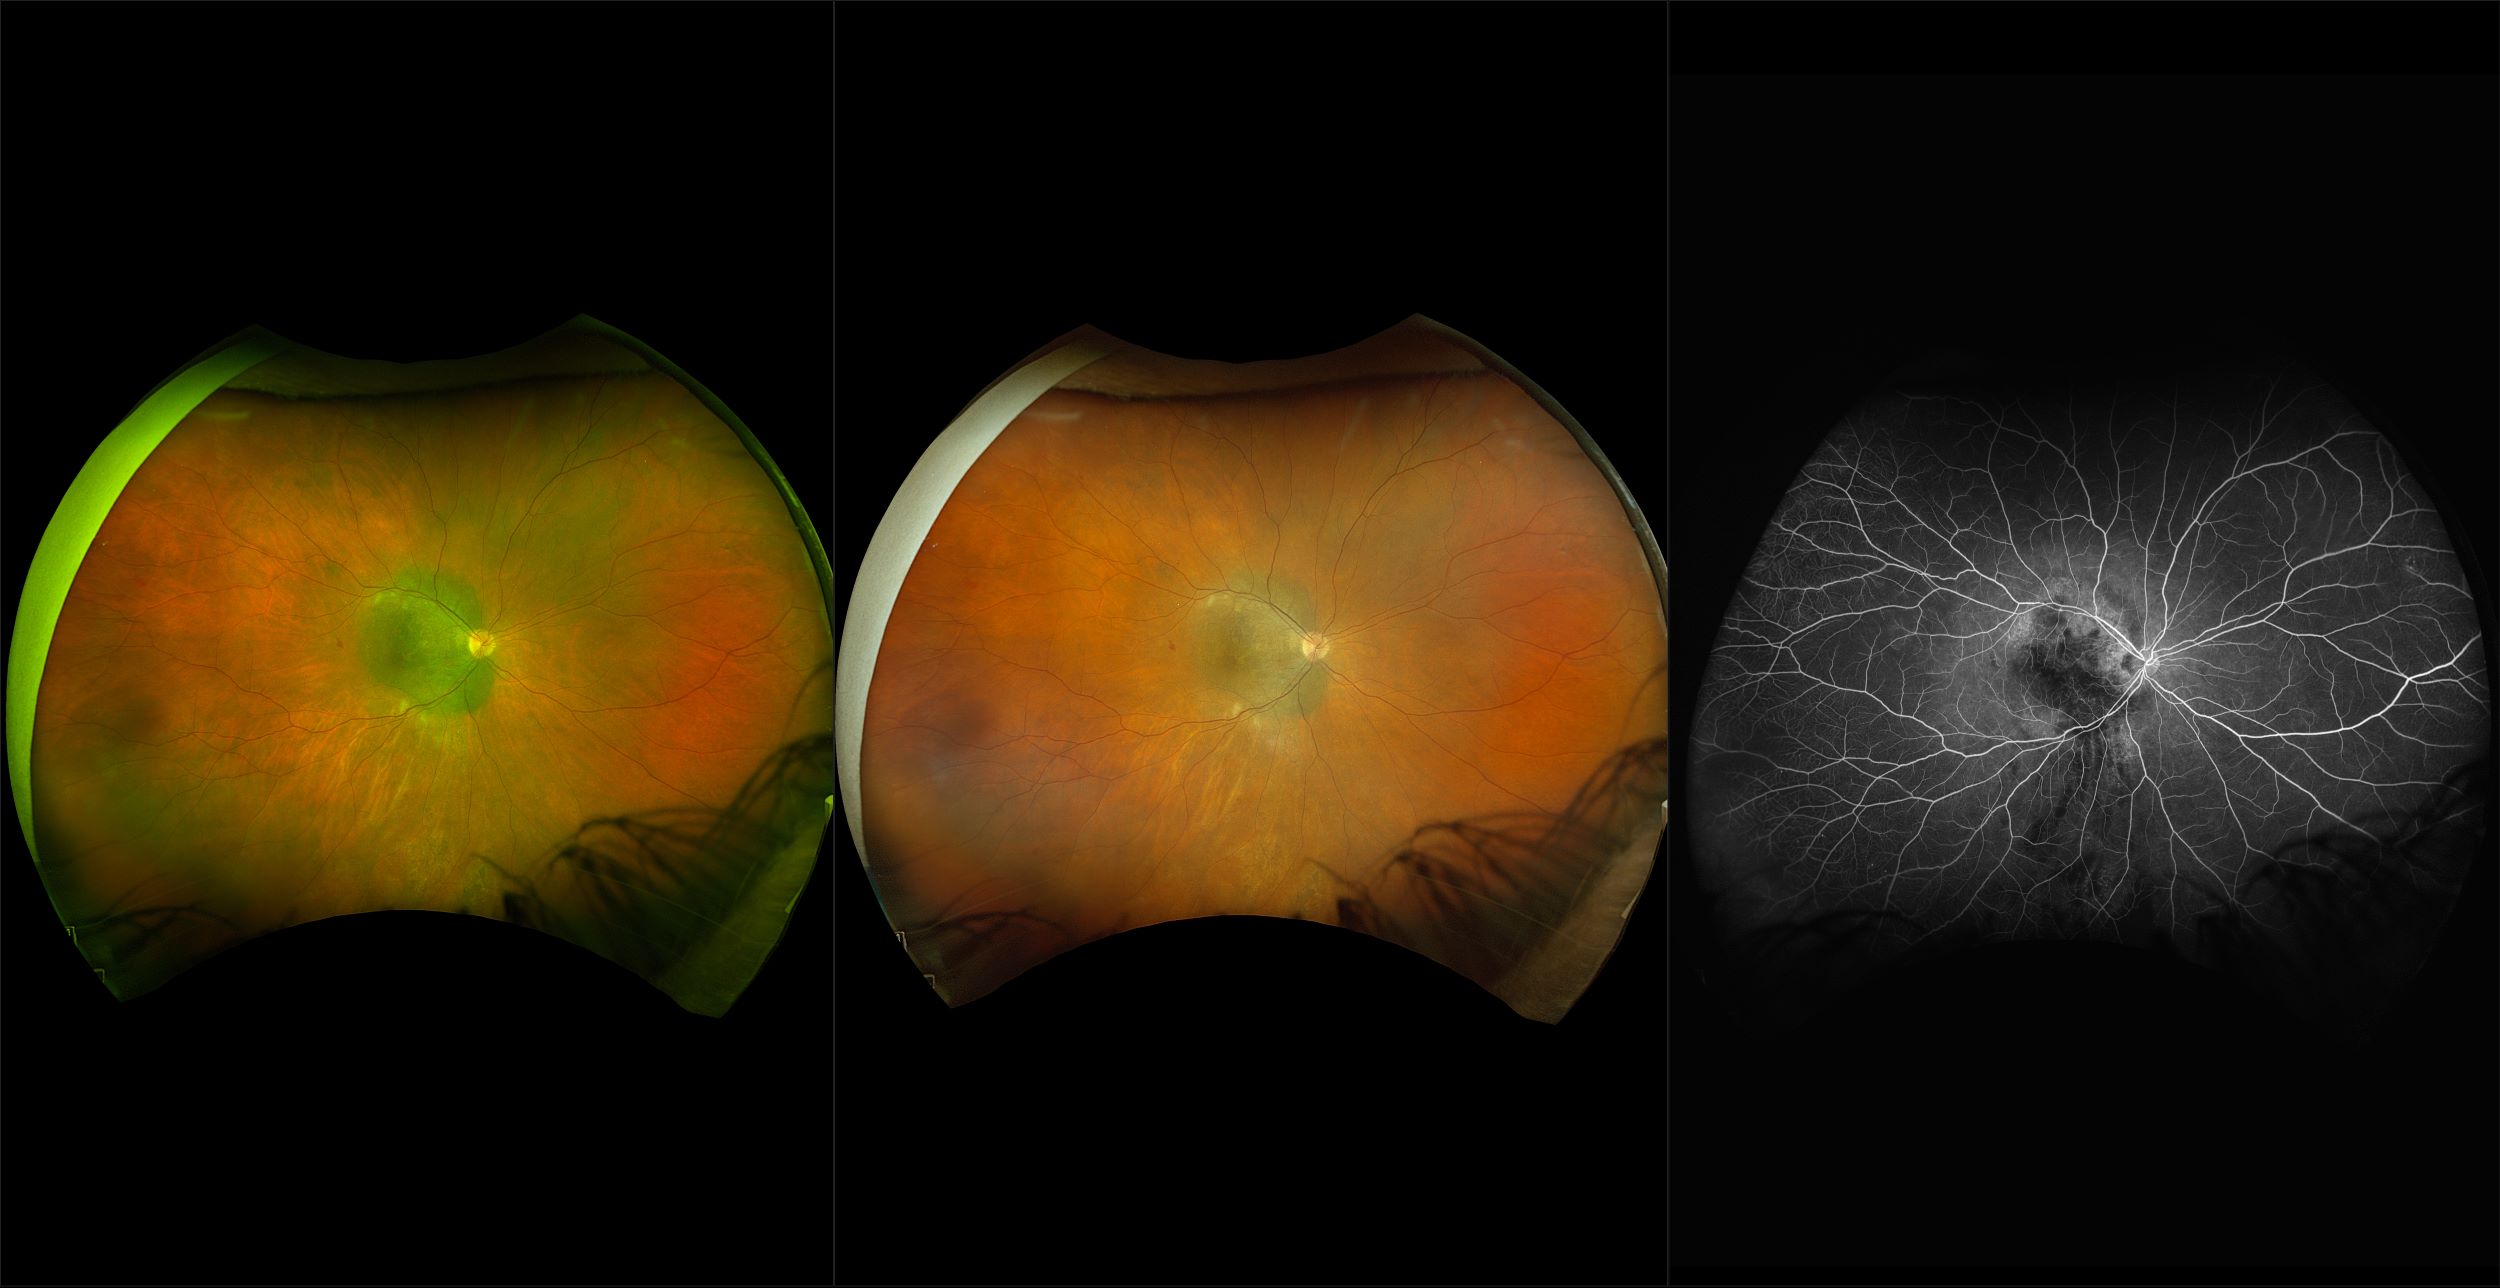

California - Choroidal Nevus, RG, AF

A choroidal nevus is simply an accumulation of melanocytes in the choroid. They are a space occupying mass or a benign melanoma. Choroidal nevi are slate gray in color, have indistinct margins, and may be slightly elevated (1-2 diopters). Since they are in the choroid, they are usually only seen in the red separation and not the green. The green separation may show the RPE degeneration associated with nevi which is seen as pigment mottling and drusen.